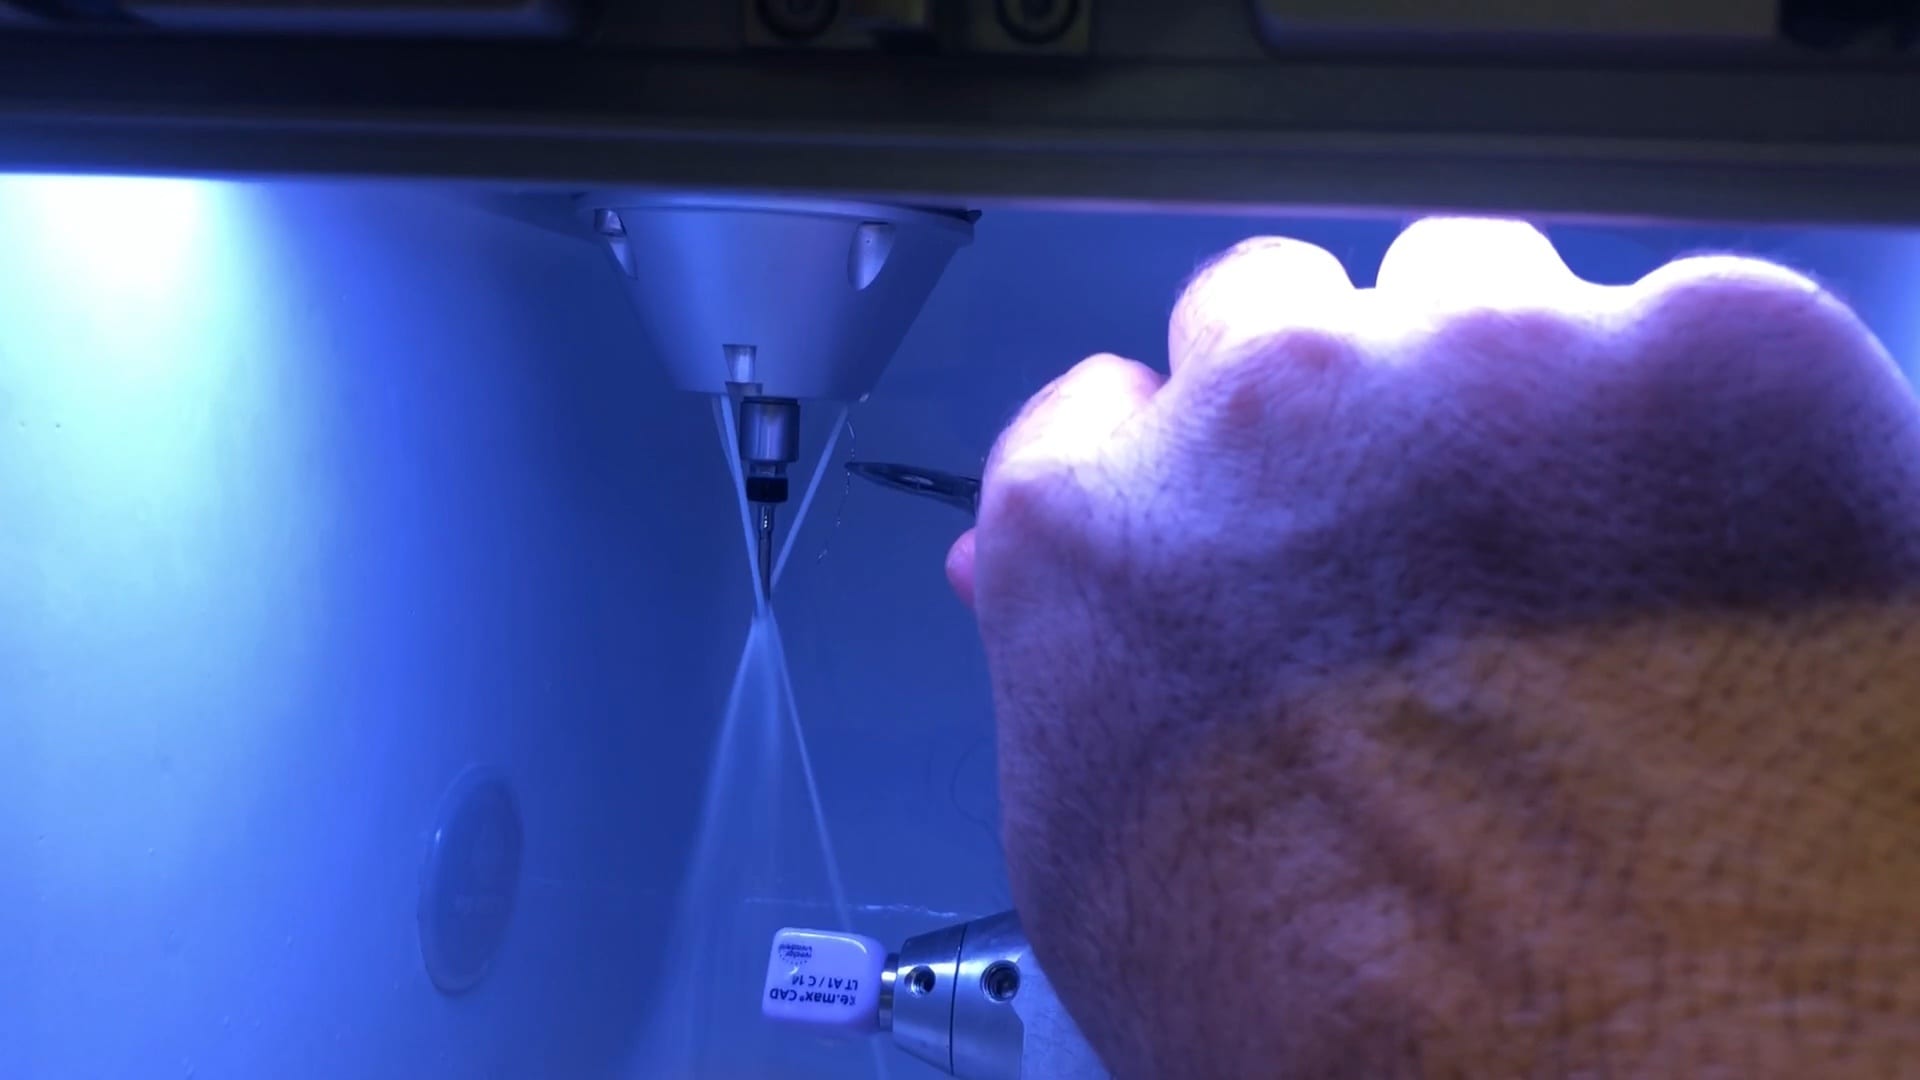

All milling machines have guidelines for proper cleaning and maintanance. The imes icore CORITEC ONE’s spray channels must be kept clean, otherwise they will spray off the target block materials. […]